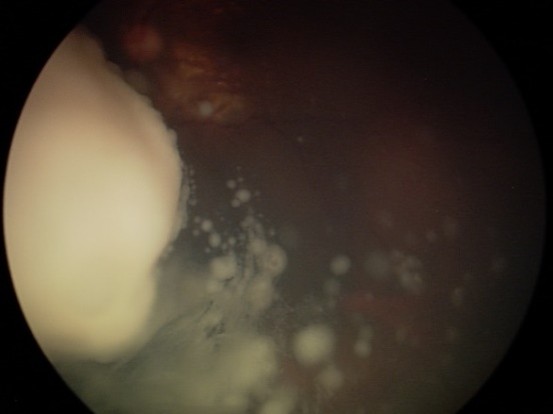

רטינובלסטומה היא גידול סרטני נדיר המתפתח ברשתית של ילדים צעירים, לרוב מתחת לגיל חמש. מדובר במחלה הניתנת לריפוי ברוב המקרים, כאשר מאובחנת בזמן. במאמר זה מסביר פרופ’ עידו (דידי) פביאן, מומחה בעל שם עולמי באונקולוגיה של העין, מהם הסימנים הראשונים למחלה, איך מתבצע האבחון ואילו טיפולים חדשניים מאפשרים לשמור על הראייה ועל חיי הילד.